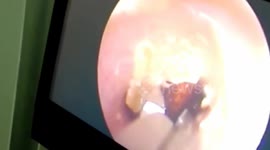

大连 蜘蛛钻进老大爷耳朵里 把耳道当成家在里面结网 素材

9月1日,辽宁大连市中心医院耳鼻喉科接诊了一位60多岁的男性患者。他的内耳道竟然有一只绿豆大小的蜘蛛在不断地动,还在耳道上结出一层白雾般的絮状物。老人称前一天晚上睡觉时耳朵进了虫子,当天上午起床时还感觉“时不时在动”。

医生立即采取措施,将这只“不速之客”清除出去。经检查,老人的耳道和听力都没有受损,医生表示,人的耳道温暖湿润,容易被一些虫子当成“温暖家园”。